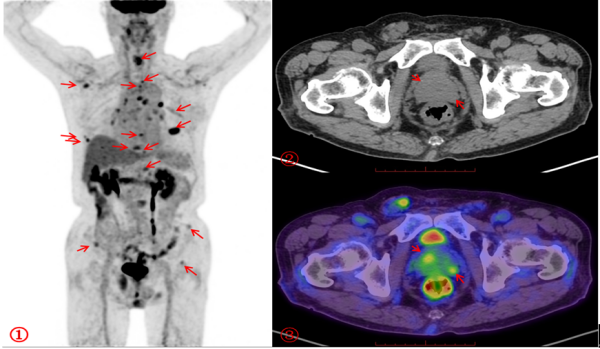

FDG PET/CT显像① MIP图:箭头所示全身多处糖代谢异常增高灶为骨转移灶;③PET/CT融合图:箭头所示糖代谢异常增高处为前列腺癌原发灶(SUVmax约3.2),而②CT图显示密度无异常。

在医生的建议下,李昌乐接受了18F-FDG PET/CT检查(18F-FDG,全称氟代脱氧葡萄糖,是一种葡萄糖类似物)。通过这种“雷达式”扫描,医生发现老人前列腺外周带代谢轻度不均匀增高,延迟显像显示进一步增高,同时全身多发骨质异常,糖代谢异常增高,其余部位未见高代谢病灶。据此,医生立即锁定“元凶”为前列腺,考虑前列腺癌伴全身多发骨转移。

为进一步明确诊断和分期,医生又为李爷爷完善了PSA(全称前列腺特异性抗原,是前列腺癌肿瘤标志物)检测,并安排了18F-PSMA PET/CT检查(PSMA,全称前列腺特异性膜抗原,是一种与前列腺癌密切相关的蛋白质)。最终,PSMA PET/CT显像清晰显示出前列腺癌原发灶及转移灶的范围及大小,并且还发现了FDG PET/CT显像未能查出的微小骨转移灶及盆腔淋巴结转移灶。这一结果为临床医生提供了关键依据,避免了盲目手术或穿刺的风险,为治疗方案选择提供了有力支持。